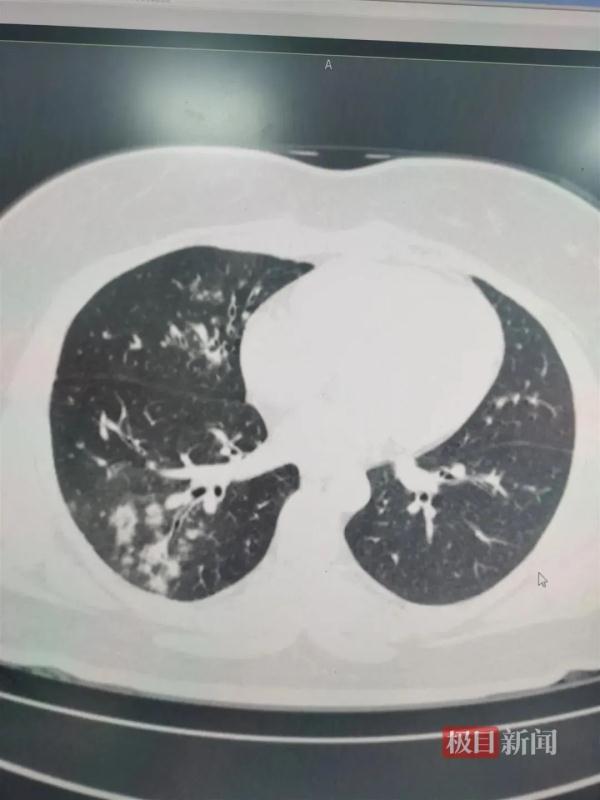

△支原体感染患者肺上呈现树雾状。

这是因为,肺炎支原体会在人体内激发出人体的免疫反应。从患者胸片,可以看到范围大小不等“白肺”的地方。

这不是说那里全是“支原体”,而主要是支原体激发出的免疫损伤、炎症浸润。